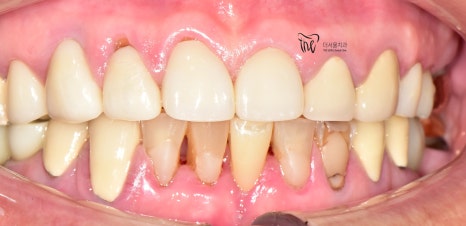

정면에서 봤을 땐, 비심미적인 모습을 보여주며

곳곳에 치경부파절증의 증세들이 드러나고

있습니다. 따라서 ,식사를 하실 때 마다

지끈거리는 통증 및 이가 시린 느낌을 지속적으로

받아오셨다 말씀을 하셨었죠.

이 분이 저희 치과에 처음 오셨을 때는,

구강 내 여러가지 문제점들을 안고 오셨었습니다.

1.치경부마모증

2.어금니 결손

3.치아 통증

등의 문제들이 많으셨었죠.